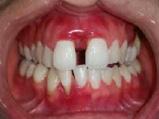

Lâexamen exobuccal Ă©tait sans particularitĂ©s. Lâexamen endobuccal a objectivĂ© une inflammation marginale modĂ©rĂ©e Ă sĂ©vĂšre gĂ©nĂ©ralisĂ©e avec un indice dâOleary Ă 68%, un indice gingival (BoP = Bleeding on Probing) Ă 76%, et un trama occlusal sur 42 (Figure 1). Le bilan parodontal montre des sites avec une profondeur de sondage (PS) de 12mm, et plus de 50% des dents prĂ©sentant une perte dâattache â„ 5mm. Le bilan radiographique a montrĂ© des pertes osseuses terminales, avec un rapport perte osseuse/Ăąge Ă 4,5 (Figure 1)

Le diagnostic de parodontite stade IV grade C généralisé a été proposé (1), avec un pronostic irrationnel au traitement pour les dents 25, 36, 42 et défavorable pour 11, 21, 35, 46 (2).

La thĂ©rapeutique Ă©tiologique a consistĂ© en une Ă©ducation Ă lâhygiĂšne bucco-dentaire, une Ă©limination des facteurs de rĂ©tention de plaque, lâextraction 42+rĂ©section radiculaire et rĂ©alisation dâune contention en fibre de verre avec la couronne ; dâune instrumentation non chirurgicale supra et sous gingivale

par quadrant (3) combinĂ©e Ă une antibiothĂ©rapie (3,4). Une chirurgie avec lambeau dâaccĂšs selon la technique du lambeau avec incision intrasulculaire (open flap) a Ă©tĂ© rĂ©alisĂ©e sur la 46. Une thĂ©rapie parodontale de soutien associĂ©e Ă une phase correctrice a Ă©tĂ© mise en place aprĂšs la thĂ©rapie parodontale active (5). La rĂ©habilitation orale a consistĂ© dans un premier temps Ă rĂ©aliser une correction orthodontique (Figure 2) ; et dans un second temps la conception dâune Ă©pithĂšse gingivale (Figure 3)

AprĂšs 6 mois, pas de profondeurs de poches â„ 6mm, avec un indice de plaque Ă 9% et un indice gingival < 10%. La thĂ©rapeutique non chirurgicale a permis un gain dâattache

stable qui sâest traduit par une diminution des profondeurs de sondage en regard de la 11, 21, et 36 dont le pronostic Ă©tait dĂ©favorable, mais aussi lâapparition dâimportantes rĂ©cessions postthĂ©rapeutique (Figure 4). La chirurgie avec lambeau dâaccĂšs a permis Ă©galement dâamĂ©liorer le niveau osseux de la 46. Le pronostic gĂ©nĂ©ral Ă long terme de la patiente a Ă©tĂ© amĂ©liorĂ©.

Figure 4 : (a) Vue clinique Ă 6 mois ; (b) bilan radiographique Ă 3mois (b) ; (c) Retro alvĂ©olaire sur la 46 avant et aprĂšs lambeau dâassainissement